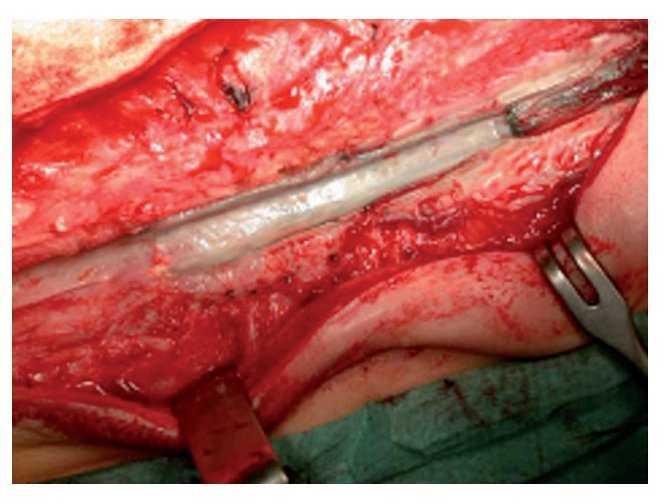

Figuras 5a y 5b. Exposición de la sinostosis costal (a) y osteotomía de la sinostosis costal con el osteótomo. El sitio de la osteotomía se distrae progresivamente con el separador laminar (b). Debe prestarse atención a desprender las adherencias costales de la pleura con un porta-algodón para que no se produzcan lesiones en la zona del pulmón.

Figura 6. El gancho costal consta de tres piezas individuales y se ensambla desde el lado proximal hacia el distal. Para acceder debajo de la costilla se usa un periostótomo para costillas.